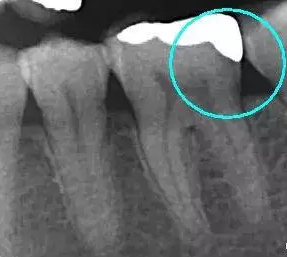

從下面這張X線中可以看出,嵌體遠(yuǎn)中邊緣沒(méi)有懸突,與牙體邊緣密合相接。